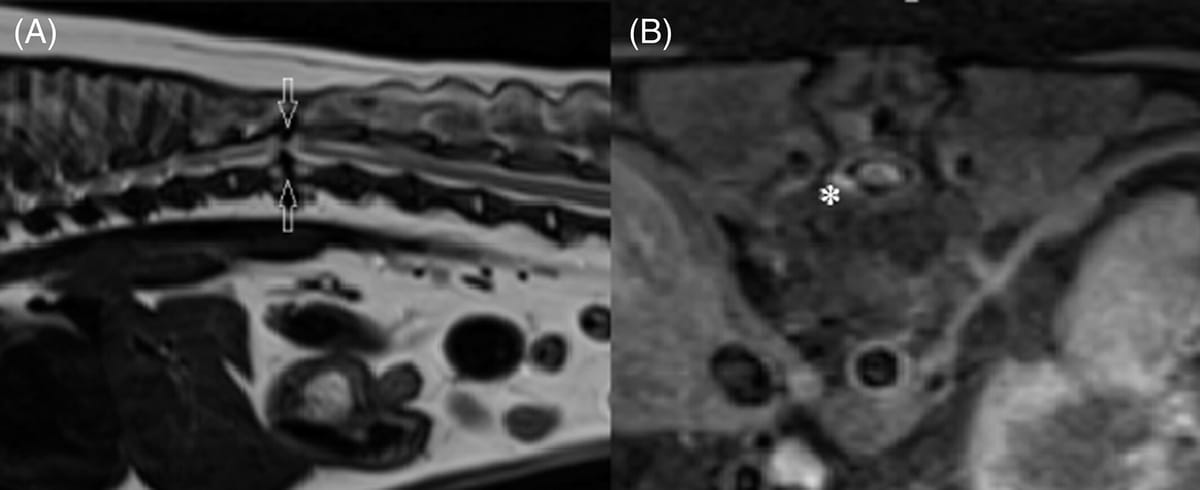

(A) Sagittal T2-weighted magnetic resonance (MR) image of the thoracolumbar region displaying a hypointense ventral and dorsal spinal cord compression and focal spinal cord atrophy at the level of T12-T13 indicated by the arrows. (B) Transverse T1-weighted fat saturated postcontrast MR image of the same dog at level of T12 displaying a hypointense band of tissue predominantly dorsolateral to the spinal cord. There is contrast enhancement of the ventrolateral meninges and spinal cord atrophy at this location indicated by the asterisk.